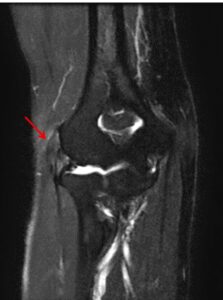

MRI検査:腱の損傷程度や、関節内の他の病変(滑膜ひだなど)との鑑別